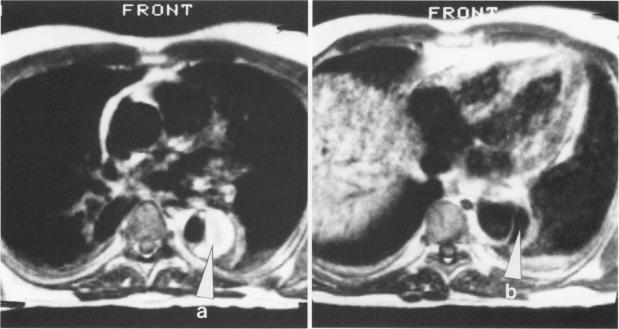

Magnetic resonance imaging is an excellent noninvasive method for evaluating thoracic aortic dissections. A variety of magnetic resonance scans of aortic dissections are shown, documenting the ability of magnetic resonance to image the true lumen, the false channel, and the intimal septum. Detail is provided on magnetic resonance imaging techniques and findings.

磁共振成像是评估胸主动脉夹层的一种出色的非侵入性方法。展示了各种主动脉夹层的磁共振扫描图像,证明了磁共振对真腔、假腔和内膜隔膜成像的能力。文中提供了磁共振成像技术及结果的详细信息。